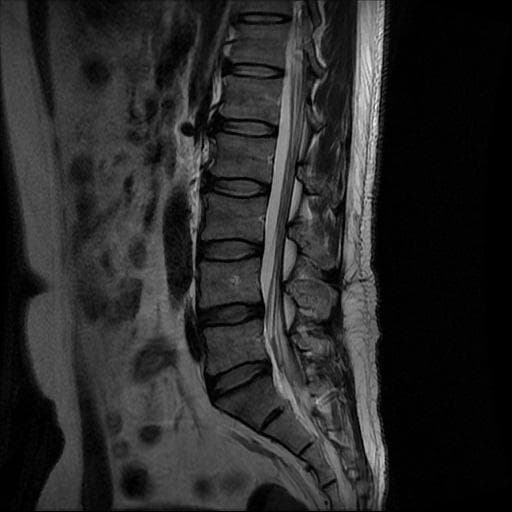

허리 MRI 디스크 상태 분석 부탁드립니다

검진 차 MRI찍었는데 분석 부탁드립니다.

건협에서는 관리해야 된다는데 디스크 협착이나 팽윤 등이 있는 상태인지 궁금합니다.

우선 현재로썬 사진만으론 판단을 하기에 제한이 되지만 사진상 디스크 상태는 심해보이지 않습니다.

요추부위의 하부 에서 약간의 팽윤이나 돌출로 의심해볼수 있는 정도이지만, 정확한 상태는 관련 전문의에게 진료시 문의를 하시는 것을 추천드립니다.